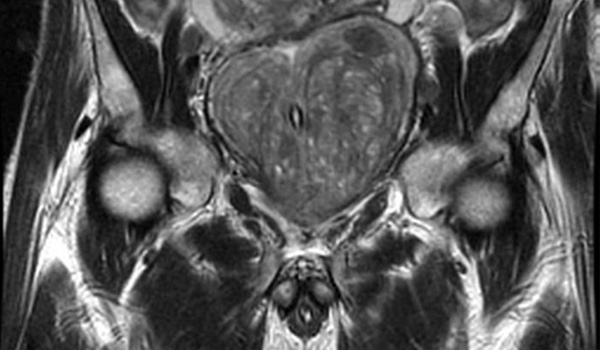

Imágenes por resonancia magnética en los exámenes de detección del cáncer de próstata: una revisión sistemática y metanálisis

Los resultados de esta revisión sistemática y metanálisis indican que la integración de la resonancia magnética (RM)  en las vías de cribado del cáncer de próstata (CaP) se asocia con un número reducido de biopsias innecesarias y un sobrediagnóstico del CaP insignificante, al tiempo que se mantiene la detección de CaP clínicamente significativos (csPCa)  en comparación con el cribado solo del PSA. JAMA Oncol 5 de abril de 2024